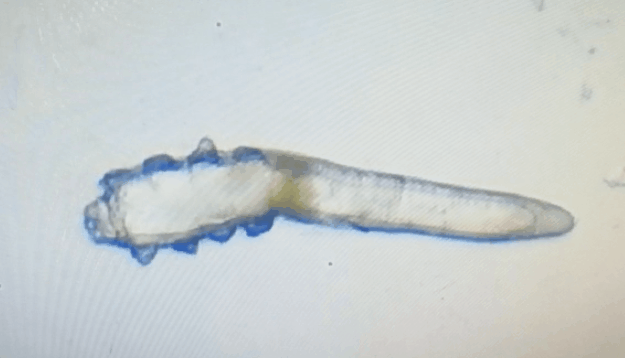

廈門眼科中心眼表及角膜病專家商旭敏博士指出:蠕形螨中的毛囊蠕形螨和皮脂蠕形螨可寄居于人體。在眼部,毛囊蠕形螨常寄居于睫毛囊,而皮脂蠕形螨多寄居于眼瞼皮膚的皮脂腺和瞼板腺。蠕形螨瞼緣炎是蠕形螨感染瞼緣所致的慢性炎性反應(yīng)性疾病,主要累及瞼緣皮膚、睫毛囊和腺體以及瞼板腺,以眼癢、眼異物感、眼干、瞼緣充血、鱗屑及睫毛根部袖套狀分泌物等為典型臨床表現(xiàn),嚴重者可引起結(jié)膜及角膜并發(fā)癥,該病可能具有一定的傳染性。

蠕形螨的危害不容小覷!??!

蠕形螨會引起睫毛異常,引發(fā)瞼緣炎性反應(yīng),瞼板腺堵塞,引起結(jié)膜炎、角膜炎等并發(fā)癥,嚴重的話將發(fā)生角膜穿孔致視力損傷甚至失明。